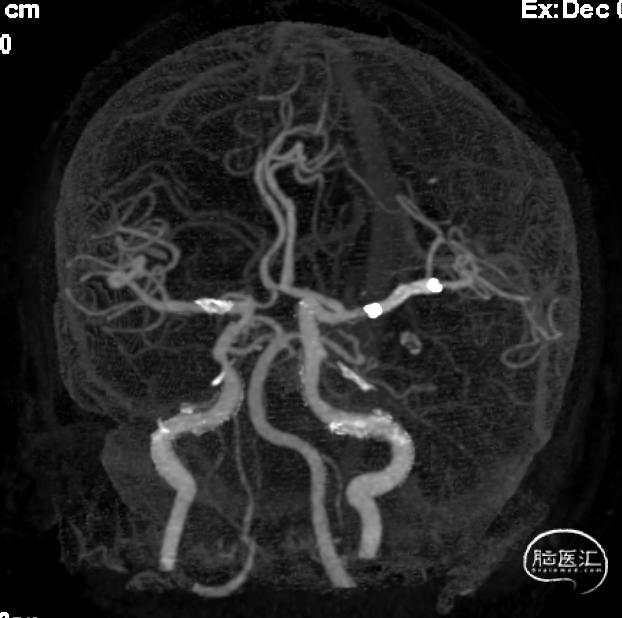

CTA

1、急性脑梗死。2、左侧大脑中动脉M1段闭塞。

ICAS合并血栓?

夹层合并血栓?

栓塞?